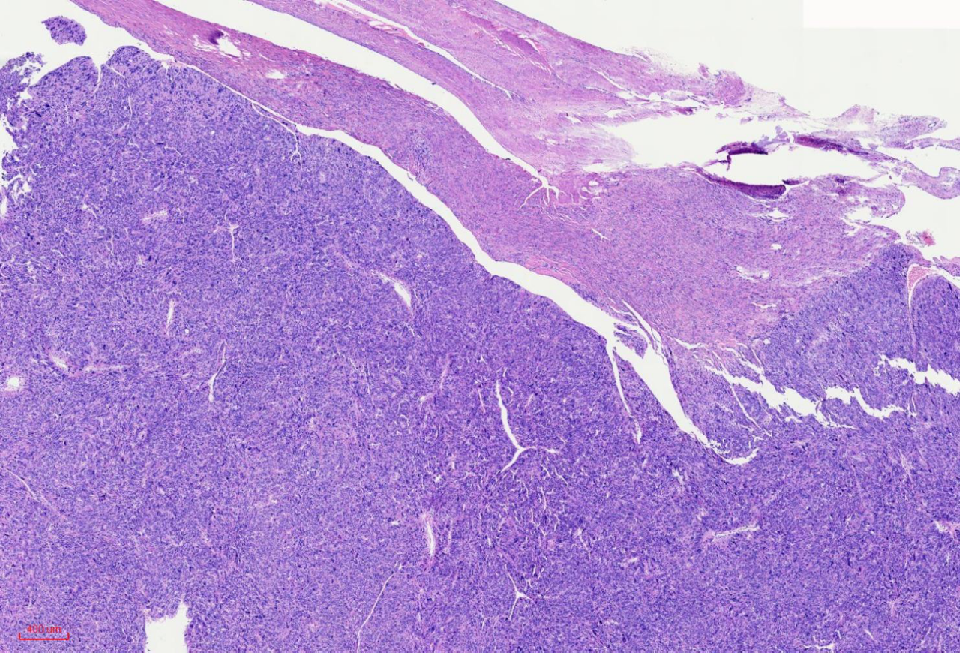

组织学改变

肿瘤与周围境界清楚

肿瘤细胞丰富

瘤细胞排列呈血管外皮瘤样

瘤细胞疏密相间

异型明显,可见核内包涵体,红核仁

未见凝固性坏死

核分裂象数2个/10HPF

肿瘤境界清楚

细胞丰富

鹿角样/血管外皮瘤样血管

肺水肿样水肿/疏密相间

细胞核奇异,嗜酸性胞质,有显著的嗜酸性核仁,核仁周围可见空晕,部分细胞呈横纹肌样

核分裂象少见

无凝固性坏死